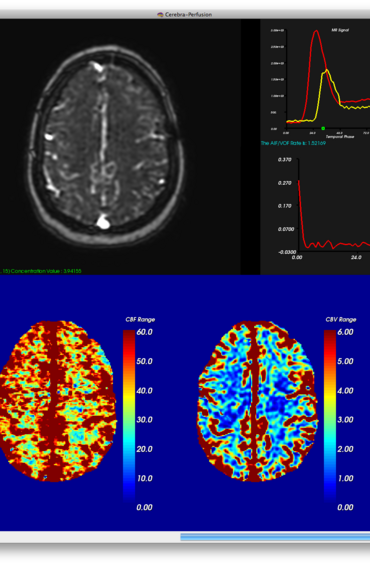

Cerebra-Perfusion

MR brain perfusion is a widely used imaging technique for quantitative analysis of cerebral microvascular hemodynamics. Cerebra-Perfusion is designed to create high-quality perfusion maps from T1-weighted dynamic contrast enhanced (DCE) or T2*-weighted dynamic susceptibility contrast (DSC) MR images.